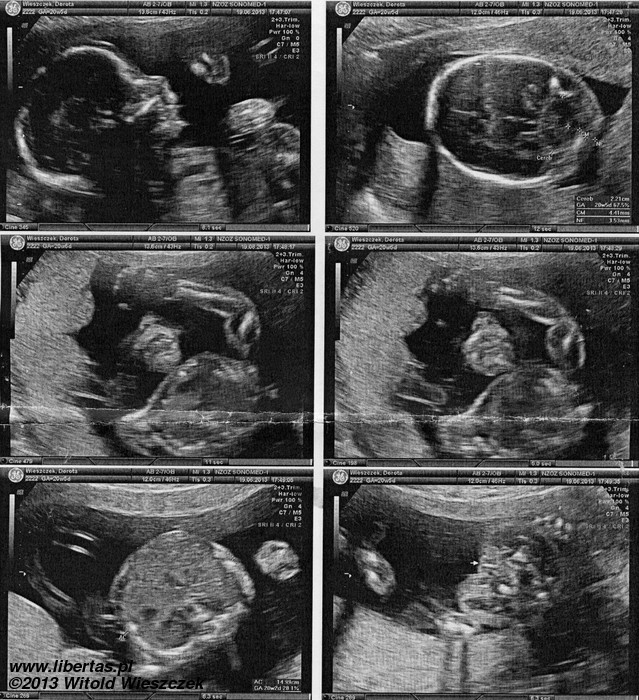

Księżniczka Dobrawa Wieszczek urodziła się 20 września 2013 roku o godzinie 8:50 w Szpitalu Wojewódzkim w Tychach. Chyba nie mogła się doczekać, bo swoje przyjście na świat przyspieszyła o ponad miesiąc, ważyła więc tylko 2140 gram i rozciągała się na długość 46 cm. Ale w skali Apgar dostała pełne 10 punktów i choć z tymi wszystkim rurkami wyglądała kosmicznie, to była zdrowa i czuła się świetnie.